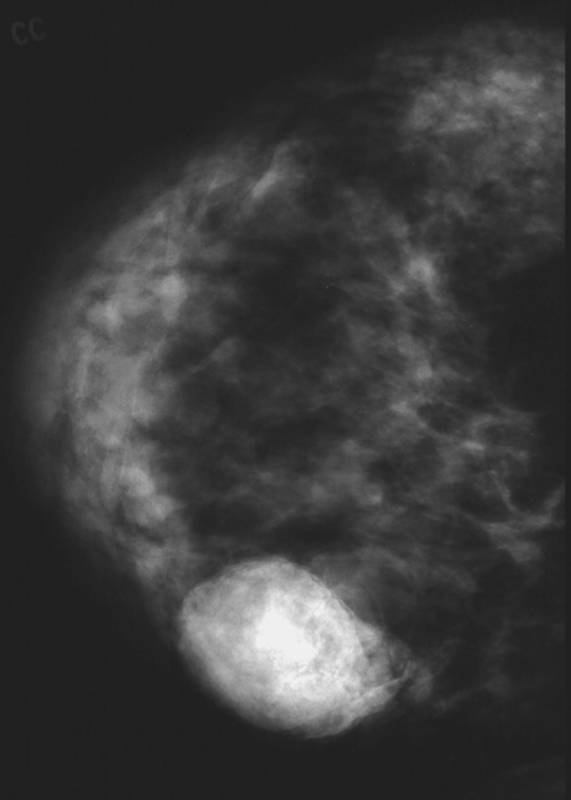

Диагностировать липому может врач хирург после визуального осмотра и пальпации места новообразования. По рекомендации врача может потребоваться УЗИ мягких тканей, маммография или биопсия с цитологическим или гистологическим исследованием.

По рекомендации врача может потребоваться УЗИ мягких тканей, маммография или биопсия с цитологическим или гистологическим исследованием.

Дуктография — контрастная рентгенография, дающая возможность выявлять мельчайшие новообразования, их локализацию и оценивать их злокачественность или доброкачественность, а также объем необходимого оперативного вмешательства.